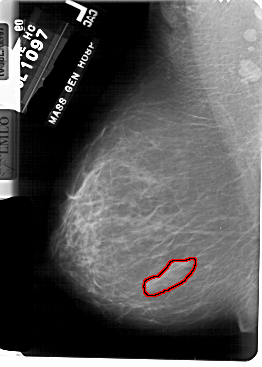

A_1756_1.LEFT_MLO

LEFT_MLO LINES 5491 PIXELS_PER_LINE 3916 BITS_PER_PIXEL 12 RESOLUTION 43.5 OVERLAY

FILE: A_1756_1.LEFT_MLO.OVERLAY

TOTAL_ABNORMALITIES 1

ABNORMALITY 1

LESION_TYPE MASS SHAPE IRREGULAR MARGINS ILL_DEFINED

ASSESSMENT 4

SUBTLETY 4

PATHOLOGY BENIGN

TOTAL_OUTLINES 1

BOUNDARY